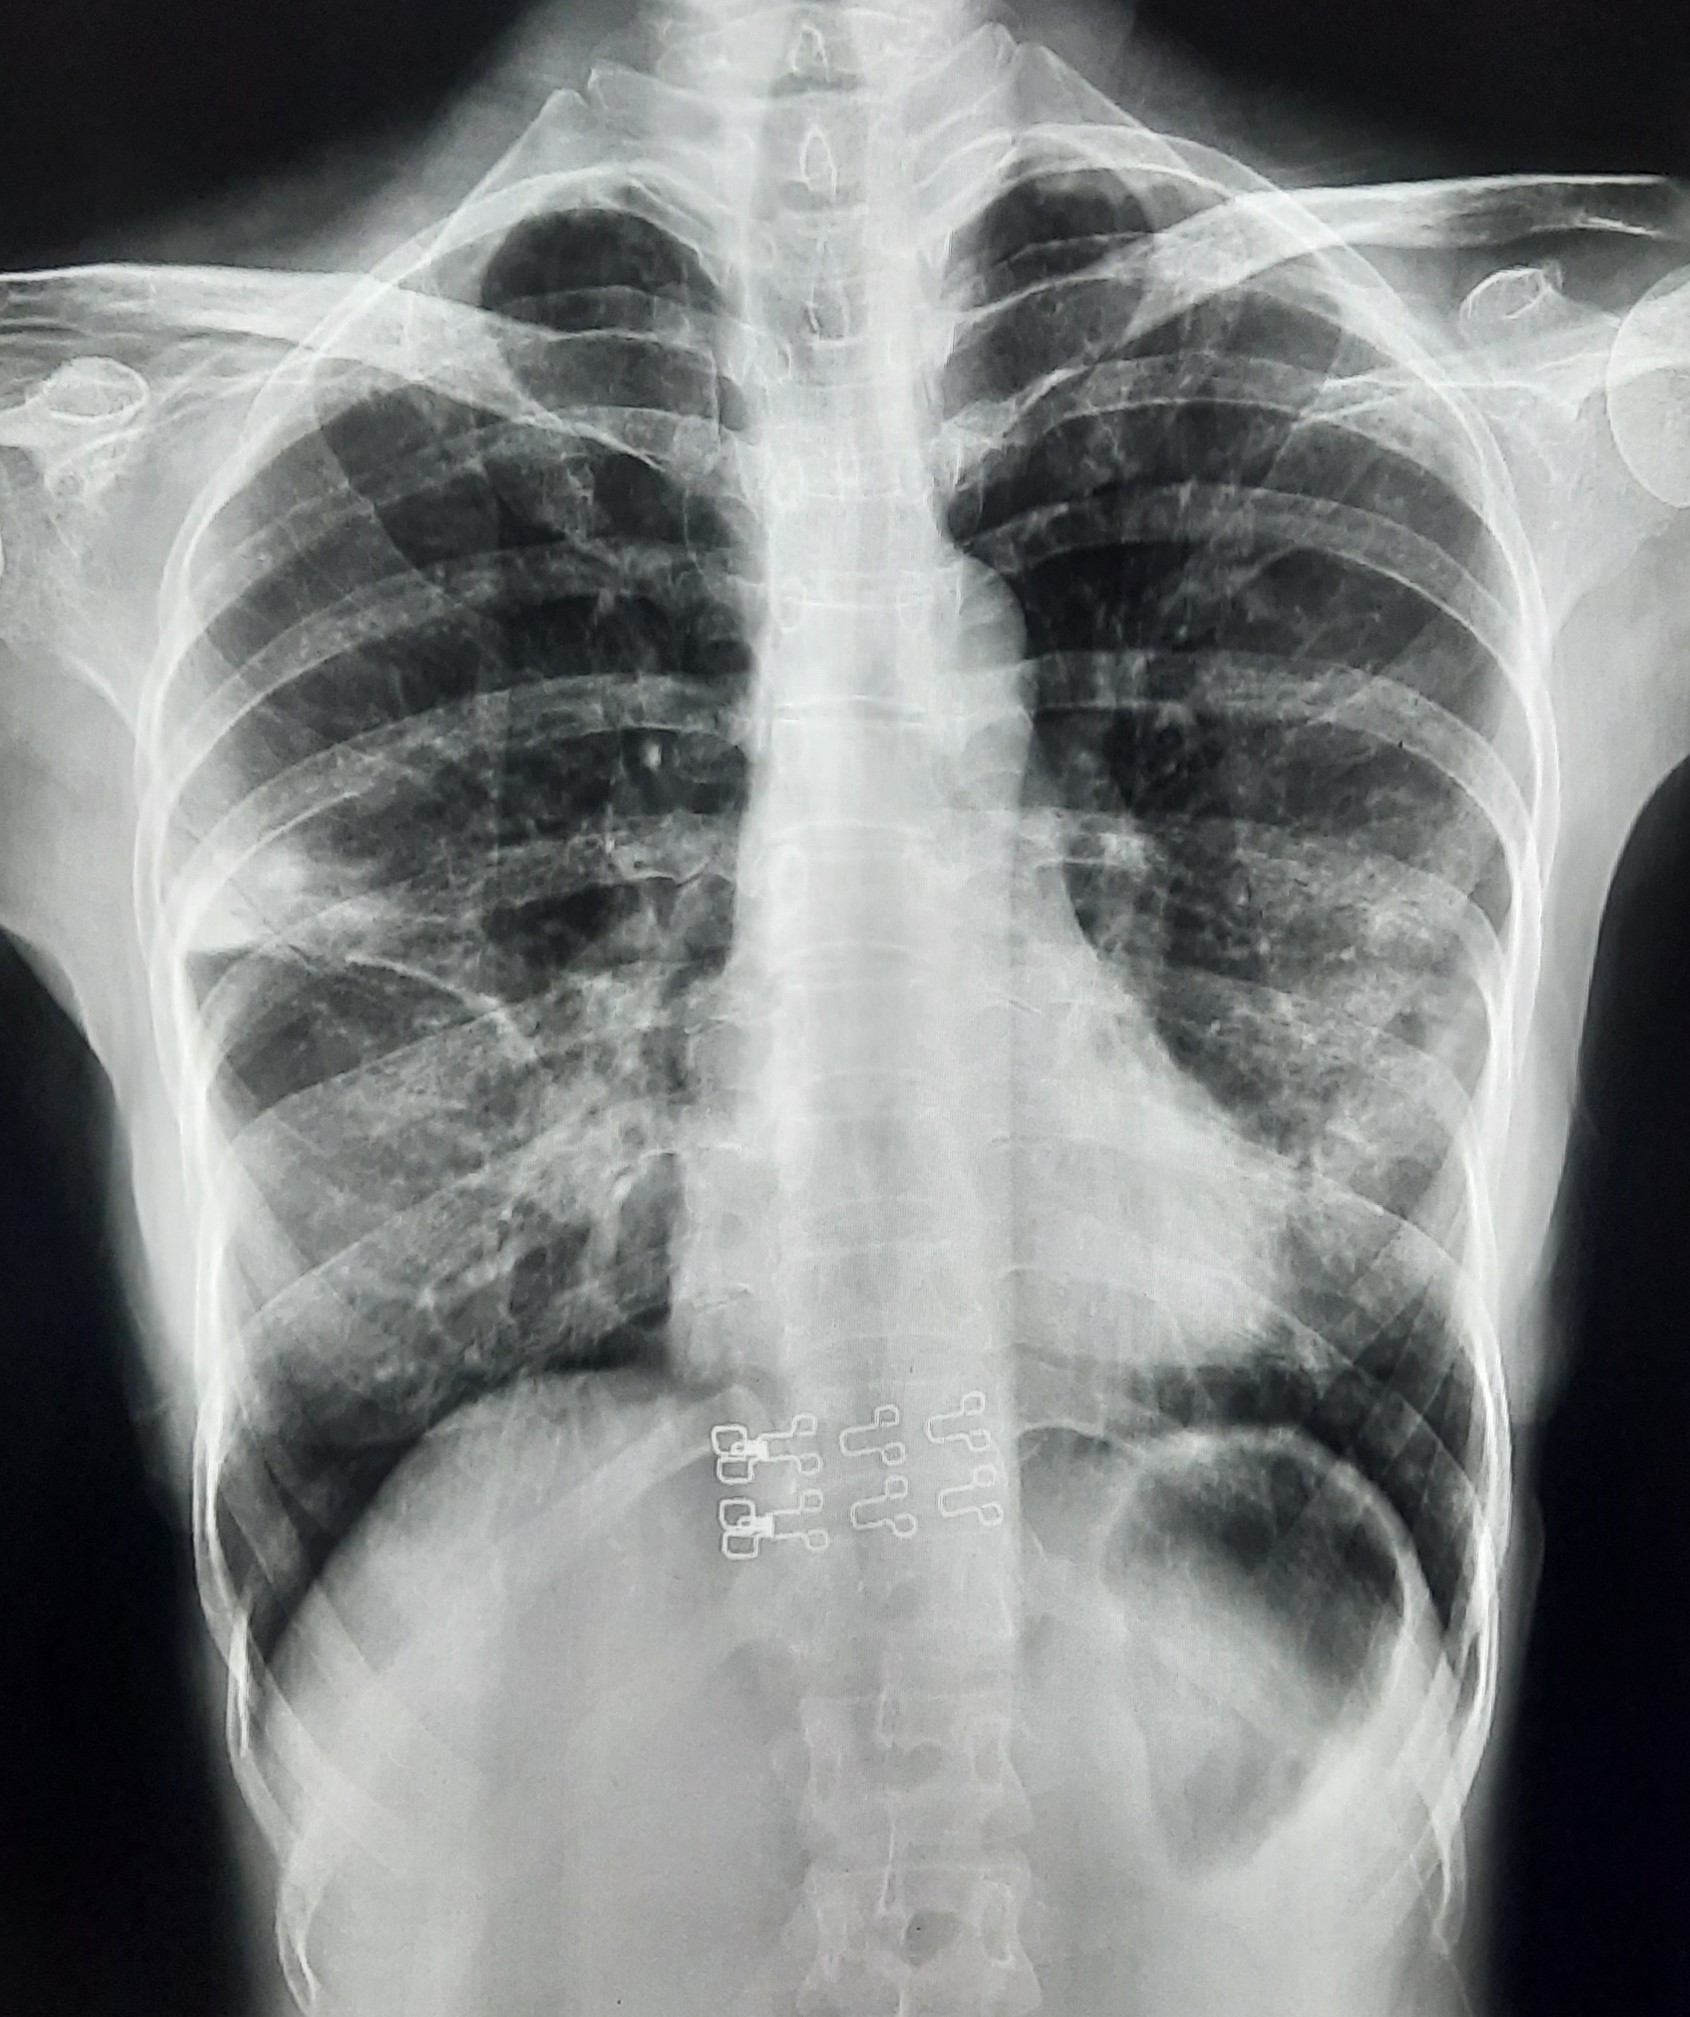

| 84 | IGGMC, Nagpur, Nagpur | P2 | 29-4388 | Dipak Panchbudhe | Consent taken on Paper | 33 Yrs. |

Provisional Diag : Pulmonary Tuberculosis Reactivation ?

Final Diag : Pulmonary Tuberculosis |

TB Case (Confirmed) | Bilateral multiple ill-defined alveolar opacity present, Left Sided Upper Zone Fibro Cavitary Lesion Present | Abnormality visible on x-ray |